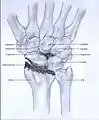

Post-traumatic osteoarthritis can be classified into four stages.[1][6] These stages are similar between SLAC and SNAC wrists. Each stage has a different treatment.

- Stage I: the osteoarthritis is only localized in the distal scaphoid and radial styloid.

- Stage II: the osteoarthritis is localized in the entire radioscaphoid joint.

- Stage III: the osteoarthritis is localized in the entire radioscaphoid joint with involvement of the capitolunate joint.

- Stage IV: the osteoarthritis is located in the entire radiocarpal joint and in the intercarpal joints. It also may involve the distal radio-ulnar joint (DRUJ).

Stage III